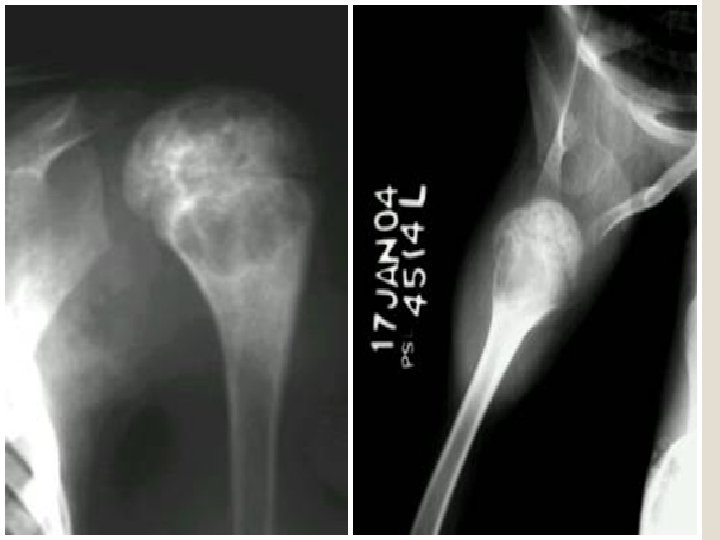

High ridding of the humerus Lateral erosion of the clavicle Marginal erosion Narrowing of the glenohumoral joint